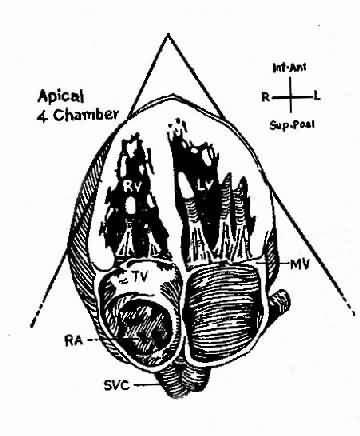

此是利用超声扫描技术 在荧光屏上显示超声波通过心脏各层结构如;心包、心肌、心内膜、室间隔、瓣膜和主动脉时发生的反射,借以观察心脏与大血管的搏动情况、房室的舒张和瓣膜开关的活动规律。目前常用的M型、B型超声心动图对二尖瓣、主动脉瓣的狭窄和关闭不全、三尖瓣狭窄,二尖瓣脱垂,特发性肥厚性主动脉瓣下狭窄,心房粘液瘤,心包积液,房、室间隔缺损等的诊断均有较大的价值。此外,利用超声心动图测量房、室腔的大小,计算心排出量、射血分数等以了解左心室功能。近年来应用彩色多普勒血流显像探查瓣膜关闭不全的返流和先心病的分流量、提高了疾病诊断质量。(图3-1-4图3-1-5)

图3-1-5 心尖四腔心切面二维超声心动图

A、照片 B、示意图